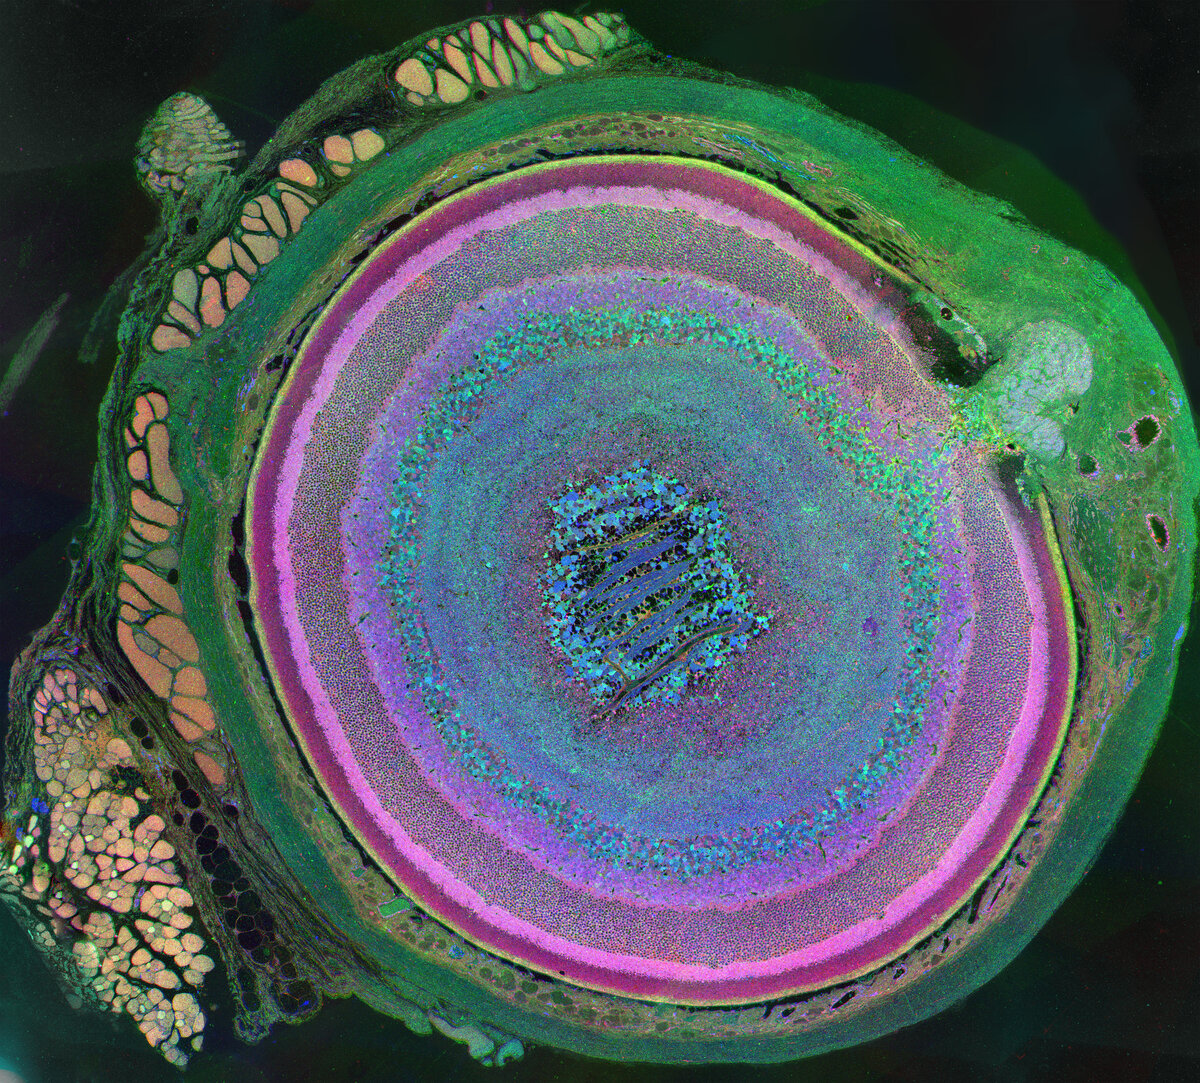

Такой сложный глаз

Перед вами — сложнейший орган нашего тела. Недаром его называют мозгом, вынесенным за пределы черепа. Современные данные свидетельствуют: в глазу, сечение которого мы здесь показываем, более 70 типов клеток, от мышечных (слева, персикового цвета), до самых разнообразных клеток сетчатки, которые в свою очередь имеют множество разновидностей. Например, только амакриновых клеток сетчатки по структурным и физиологическим критериям выделяют более 20 типов (и до сих пор неизвестно, зачем организму столько). Так что глаз еще не открыл нам все свои секреты. Credit :Bryan William Jones and Robert E. Marc, University of Utah

Credit :Bryan William Jones and Robert E. Marc, University of Utah